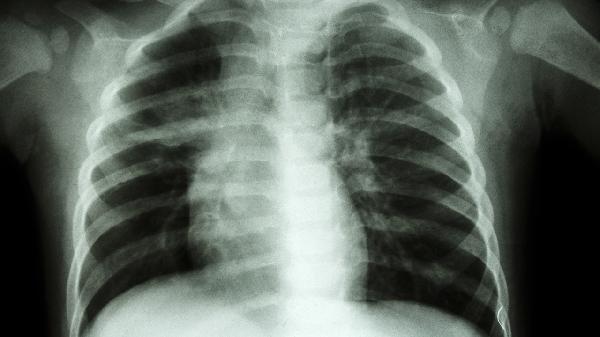

气管受压可能由肿瘤、甲状腺肿大或纵隔病变引起。压迫导致气管狭窄,呼吸时气流不畅,引发胸痛。治疗需针对原发病,如手术切除肿瘤、甲状腺激素调节左甲状腺素,或放疗化疗控制纵隔病变。

气管感染如结核或真菌感染,可导致气管壁损伤,引发胸痛。治疗需使用抗结核药物异烟肼、利福平或抗真菌药物氟康唑、伊曲康唑,同时加强营养支持。